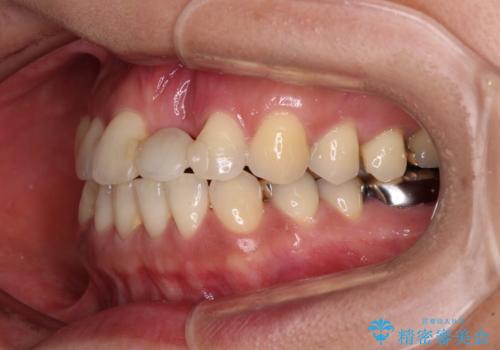

矯正治療により前歯横幅のバランスを整えた後に、上顎前歯をオールセラミックブリッジにて補綴治療を行うこととしました。

中途半端な矯正治療と前歯の欠損 再矯正とオールセラミッククラウンによる補綴治療